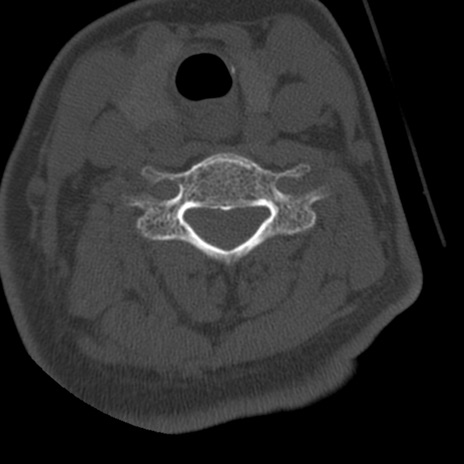

症例50 頚椎CT(横断像)

異常所見と診断は?

頚椎CT